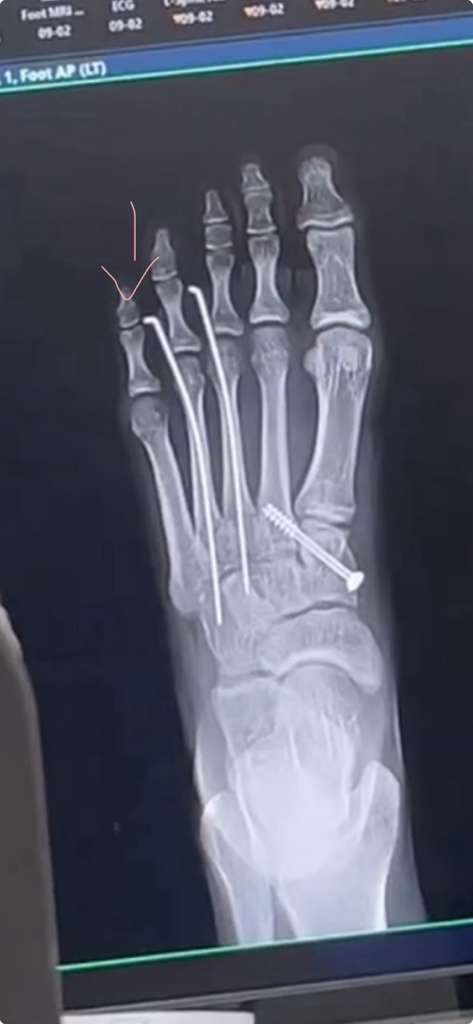

체중부하를 하거나, 앞쪽 관절에 의해 압박이 오기 때문에 옆으로 휘는 것은 정상적으로도 볼 수 있습니다.

하지만 새끼 발가락에 상처등이 생기고 통증이 있으시다면 핀의 위치를 일부 조절 받으시는 것이 좋겠습니다.